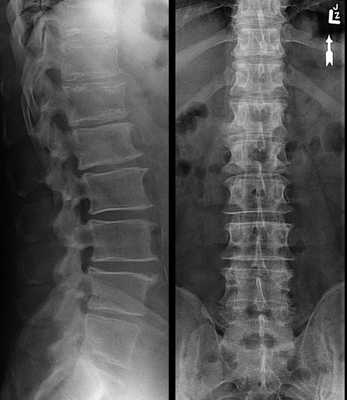

РИСУНОК 1 Рентгенограмма поясничного отдела позвоночника в ПЗ проекции, демонстрирующая правильное его расположение.

• Видны поясничные мышцы

• Остистые отростки располагаются по срединной линии тел позвонков на равном расстоянии от корней дуг позвонков

• Крестец и копчик визуализируются по центру входа в малый таз (рис. 3)

• Сколиоз: рис. 4 и 5

• Межпозвонковые щели открыты

• Отсутствует дисторсия тел позвонков (см. рис. 6, 7 и 8)

• Продольная ось поясничного отдела позвоночника совмещена с продольной осью экспозиционного поля

• Позвонок L3 находится в центре экспозиционного поля

• Экспозиционное поле 20x43 см: в поле входят 12-й грудной, 1-5 поясничные позвонки, крестцово-подвздошные суставы, крестец, копчик и поясничные мышцы

• Экспозиционное поле 20x35 см: в поле входят 12-й грудной, 1-5 поясничные позвонки, крестцово-подвздошные суставы и поясничные мышцы

РИСУНОК 2 Правильное положение пациента для рентгенографии поясничного отдела позвоночника в ПЗ проекции. РИСУНОК 3 Рентгенограмма поясничного отдела позвоночника в ПЗ проекции. Левая сторона располагалась к ПИ ближе, чем правая.

РИСУНОК 4 Рентгенограмма поясничного отдела позвоноч ника в ПЗ проекции при выраженном сколиозе. РИСУНОК 5 Рентгенограмма поясничного отдела позвоночника в ПЗ проекции при слабом сколиозе. РИСУНОК 6 Рентгенограммы поясничного отдела позвоночника пациента в боковой и ПЗ проекциях. Показано положение межпозвонковых щелей. РИСУНОК 7 Положение ЦЛ и поясничных позвонков при разогнутых нижних конечностях. РИСУНОК 8 Рентгенограмма поясничного отдела позвоночника в ПЗ проекции при разогнутых тазобедренных и коленных суставах. РИСУНОК 9 Положение ЦЛ и поясничных позвонков при согнутых нижних конечностях.